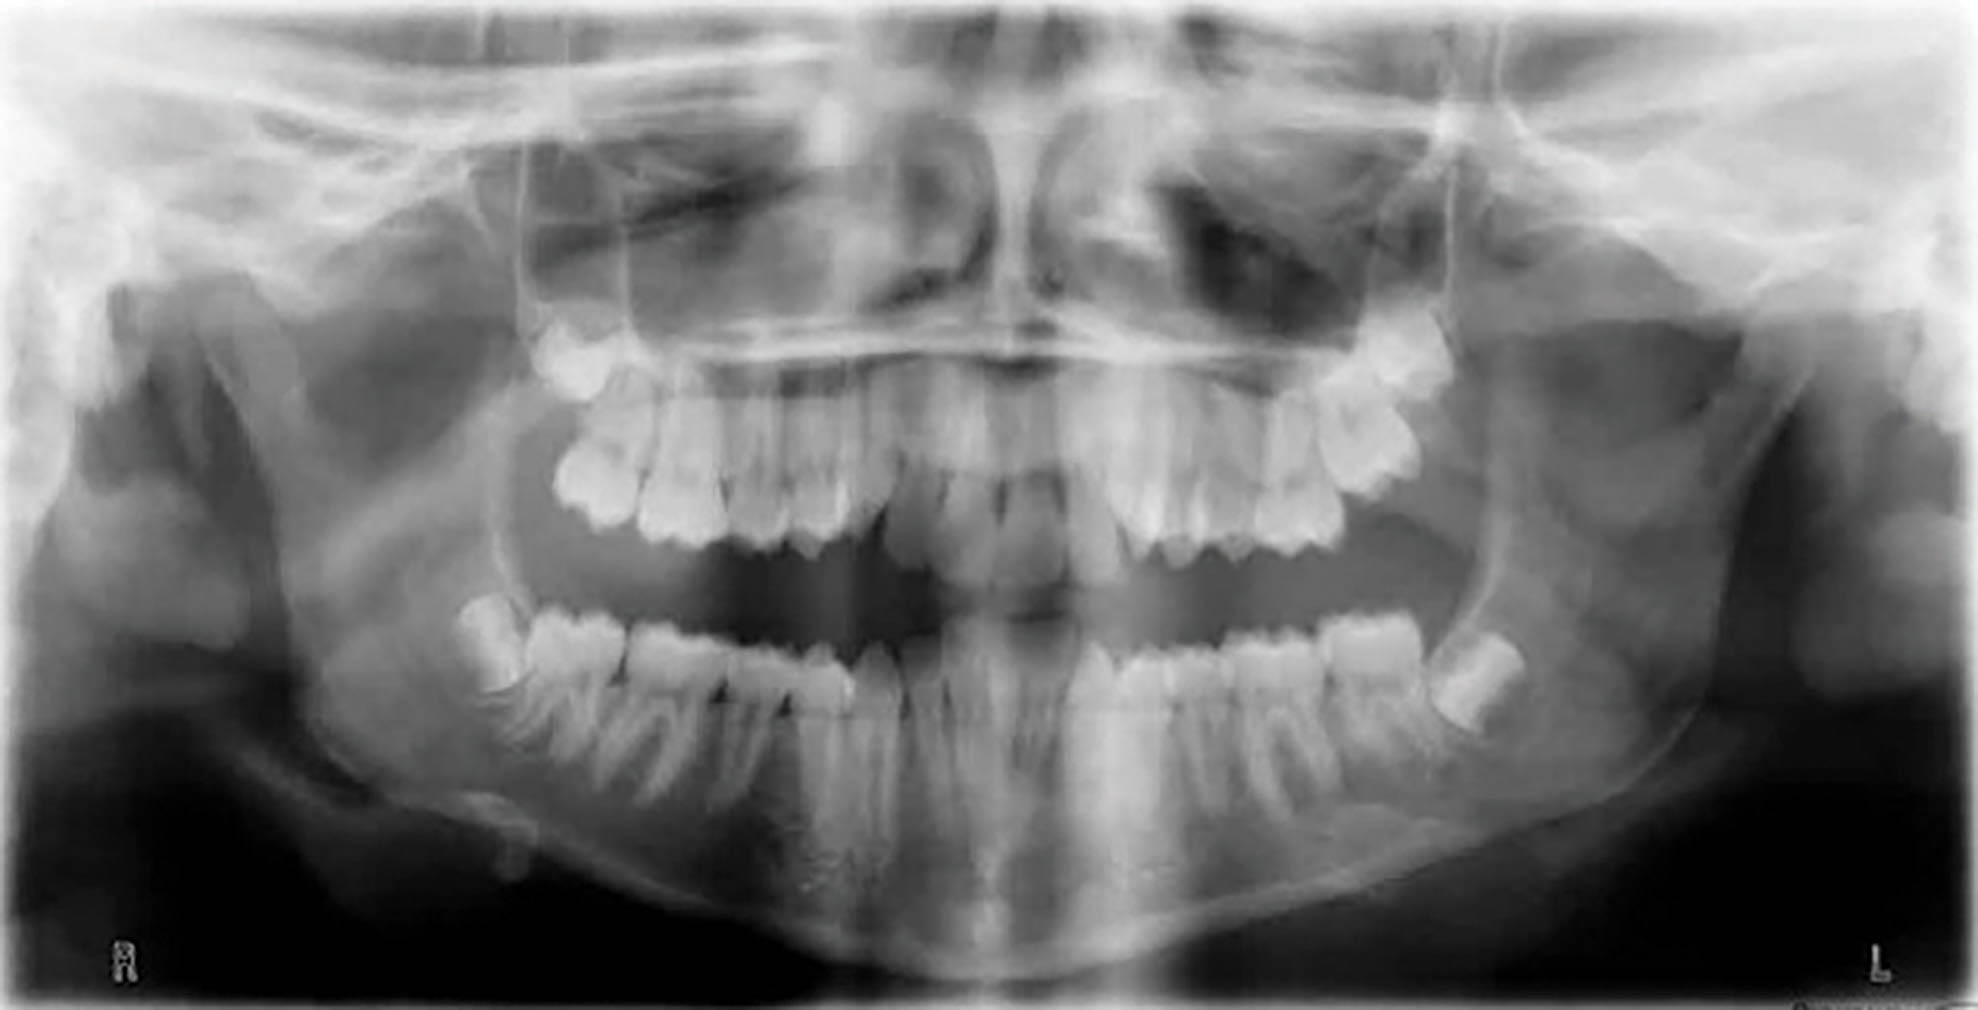

بیمارClII/2 با دیپ بایت شدید و ارتفاع عمودی کم صورت است (شکلهای 73-6 الی 75-6).

شکل 73-6

شکل 74-6

شکل 75-6

در چک لیست درمان مشاهده میکنید که انسیزورهای رترود شده بالا نیاز به اینتروژن نسبی (به کمک پروترود شدن) دارند، در حالیکه انسیزورهای پایین نیاز به اینترود شدن مطلق دارند تا کرو اسپی صاف بشود. علاوه بر این، نیاز به اکستروژن خلف هم داریم تا ارتفاع عمودی صورت بیشتر گردد. از بایت پلیتهای قدامی برای حذف نیروهای اکلوزالی (که مانع اصلاح دیپ بایت و اکستروژن خلف است) استفاده نمودیم.

دیپ بایت و رابطه ClII/2 به کمک الاستیک کلاسII در طی ۴۰ ماه درمان گردید (شکل 76-6 الی 78-6). برای نحوه درمان روابط افقی به مبحث بُعد افقی مراجعه کنید